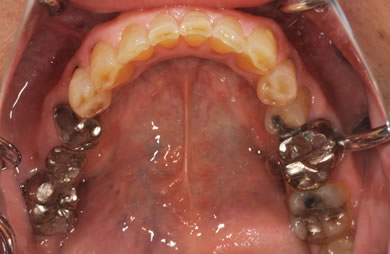

治療前

• 治療前